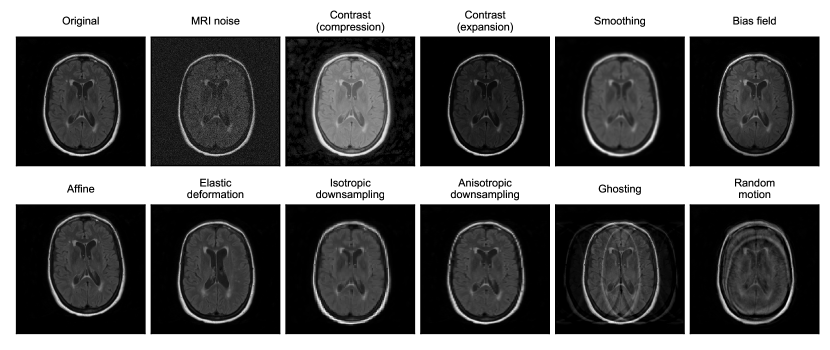

Refer to caption

Figure 2: Transforms used to model OOD data, corruptions, and artifacts in MRI. In this figure, transforms are applied to a FLAIR image for a patient with periventricular WMH lesions (original image prior to transformations shown in top left).

We simulate distribution shifts and corrupted data by applying transforms to images from a clean test set (Figure 1). We refer to the transformed test set as a benchmarking dataset. As shown in Figure 2, we selected 11 different transforms that cover distribution shifts across multiple categories discussed previously: (1) signal-to-noise ratio (SNR); (2) contrast and intensity non-uniformity; (3) image resolution and blurring; (4) spatial location of features (e.g., translations, rotations, deformations); (5) presence of motion artifacts. Ground truth segmentations were transformed accordingly and re-discretized for spatial transforms that alter the shape or orientation of the feature of interest (e.g., affine, elastic deformation, downsampling). Transforms were sourced from the Medical Open Network for AI (MONAI)222https://monai.io/ and TorchIO333https://torchio.readthedocs.io/ [Pérez-García et al., 2021] libraries, both part of the PyTorch Ecosystem [Paszke et al., 2019], or implemented where implementations were unavailable (e.g., for MRI [Rician] noise). See A for full descriptions of each transform and their formulations.